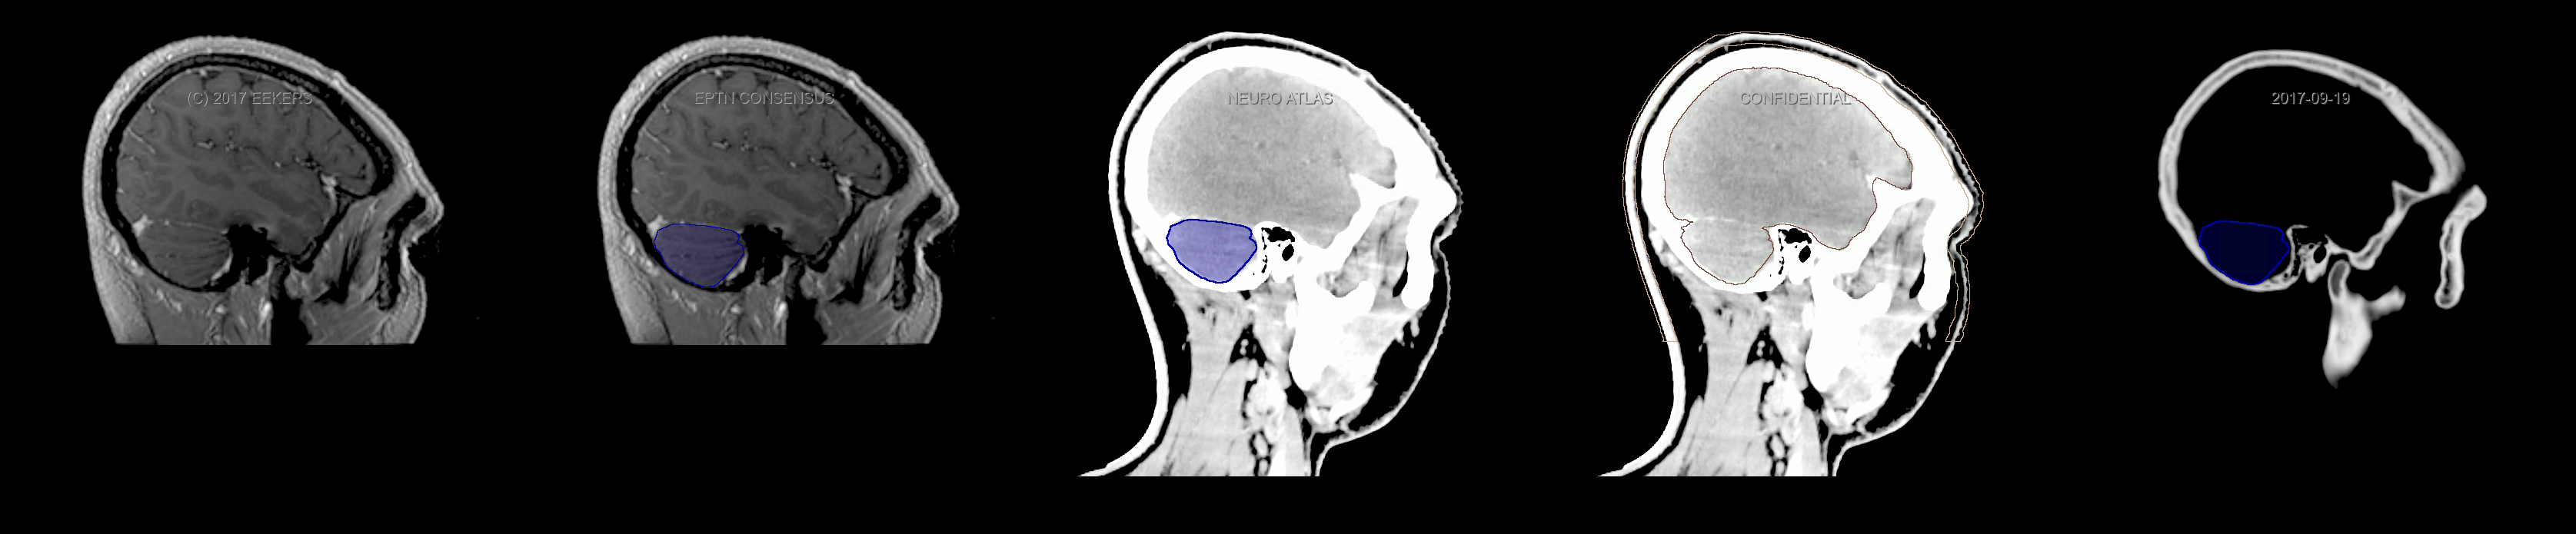

Eekers et al. have published an international neurological atlas for contouring of organs at risk in consensus with the European Particle Therapy Network (EPTN). The purpose of this consensus atlas is to decrease inter- and intra-observer variability in delineating OARs relevant for neuro-oncology. We propose this atlas is used in photon and particle therapy in order to derive consistent dosimetric data. When required this atlas will be updated according to new insights.

Included are all OARs known to be relevant for radiation-induced toxicity in neuro-oncology: brain, brainstem, cochlea, vestibulum & semicircular canals, cornea, lens, retina, lacrimal gland, optic nerve, chiasm, pituitary, hippocampus and skin. A new OAR relevant for neuro-cognition, the posterior cerebellum is also included.

Three-dimensional delineation of the fifteen consensus OARs for neuro-oncology are shown on CT and 3 Tesla (3T) MR images (slice thickness 1 mm with intravenous contrast agent). All are presented in transversal, sagittal and coronal view.

From left to right: MR without structures, MR with structures, CT (WW/WL 120/40) with structures, CT (WW/WL 120/40) with Brain and Brainstem Surface, CT (WW/WL 1500/120)with structures